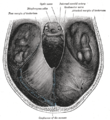

| The left optic nerve and the optic tracts. | |

The fornix and corpus callosum from below.